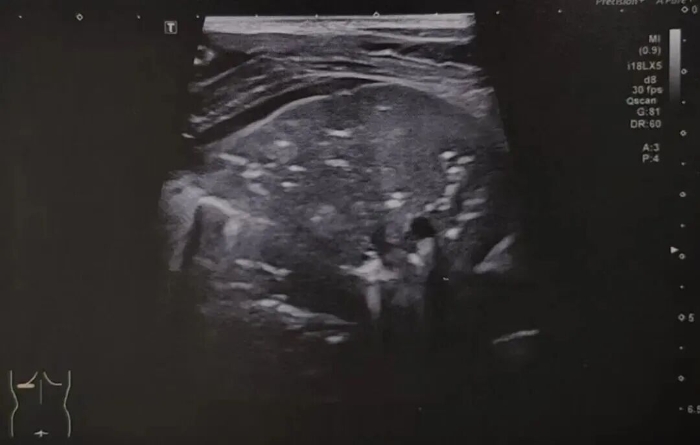

肺炎: 这是最主要的适应症。超声下能看到因炎症渗出导致的“肺实变”、支气管内的含气征,就像在肺里看到了“树枝”一样。